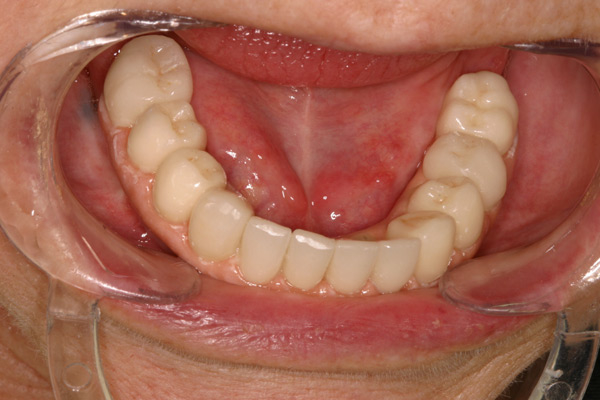

Problem: This patient presented with severe decay and a difficult occlusion/bite. He had teeth that had already been removed.

Plan: Our plan… remove the rest of the teeth and place an upper denture. Place four implants on the lower using guided surgery. Restore with a fixed/hybrid bridge.

A solution to every problem.